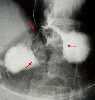

A case of type 2 advanced gastric cancer which developed in the remnant stomach.

X-ray